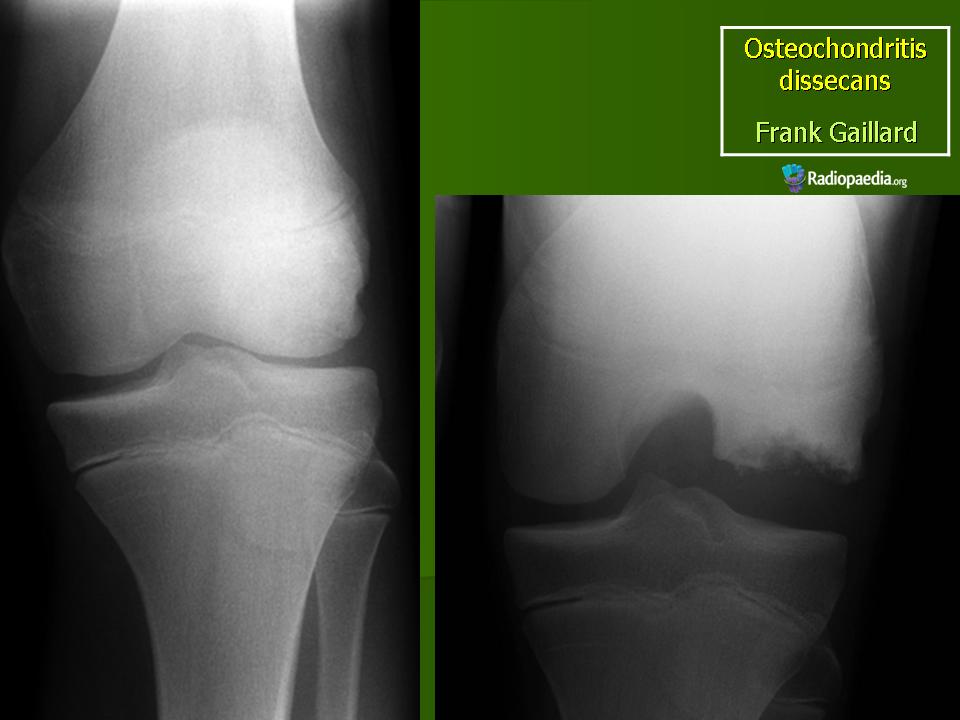

Рентгенологически в I стадии в субхондральной зоне выпуклой суставной поверхности мыщелка бедра выявляется ограниченный участок уплотнения кости. Обычно он двояковыпуклый, достигает размеров 1,0×1,5 см и ограничен узким ободком просветления. Затем (во II стадии) происходит отграничение уплотненного костно-хрящевого фрагмента от материнского ложа: расширяется зона просветления вокруг него, фрагмент начинает выступать в полость сустава (рис. 10). В III стадии определяется ниша в области суставной поверхности мыщелка бедренной кости, а внутрисуставное тело обнаруживается в любой части коленного сустава (обычно, в одном из заворотов, а при блокаде сустава - между суставными поверхностями).

В 90-93% случаев заболевание поражает коленный сустав, в основном внутренний мыщелок бедра. Патологический очаг может также локализоваться в области головки бедра, головки плеча, дистального эпифиза плечевой кости - болезнь Паннера (1929), головки луча, локтевого отростка, тела таранной кости - болезнь Диаза (1928), тела позвонка, головки I плюсневой кости.